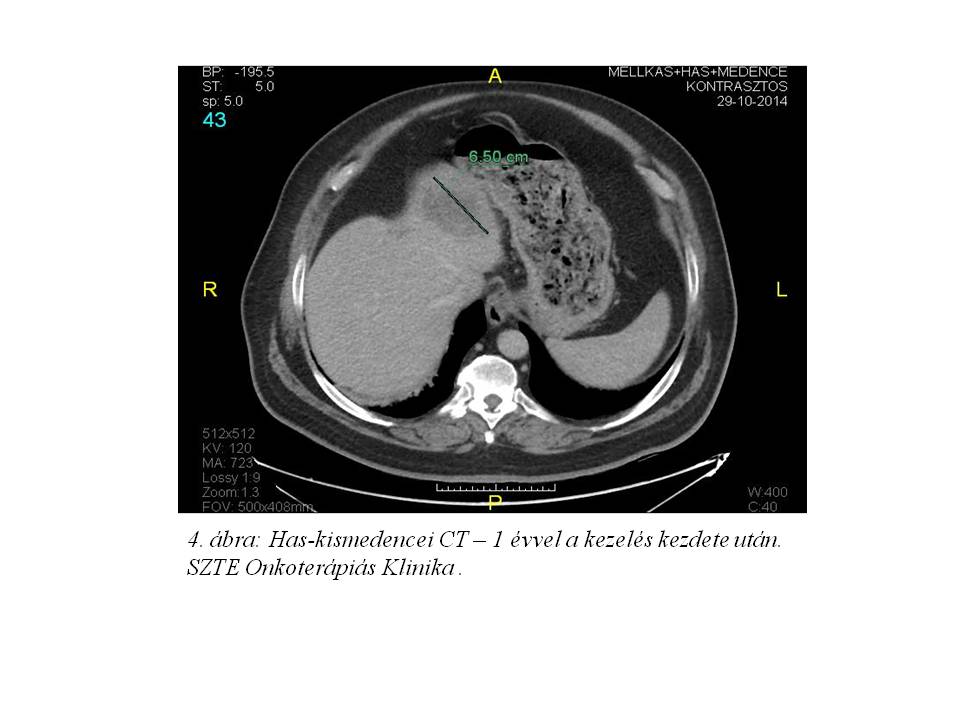

Az első staging mellkasi CT vizsgálat 3 hónap után részleges regressziót írt le (3. ábra), majd további javulást figyelhettünk meg (4. ábra, 5. ábra).

Az elsődleges máj daganat RECIST 1.1 szerint értékelve 1 évvel a kezelés megkezdése után mutatott részleges válaszadást.